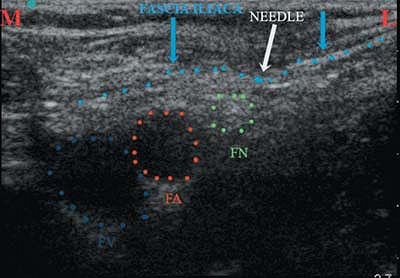

![]() |

|

Figure 43-9.

The femoral vein and femoral artery lie medial to the femoral nerve, underneath the fascia iliaca. The distance between the femoral nerve and the femoral artery varies, depending on the child’s age. FN, femoral nerve; FA, femoral artery; FV, femoral vein. |

Figure 43-10.

Indentation of the fascia iliaca by the block needle as it is advanced toward the femoral nerve. Because of the thinness of the fascia iliaca in children, it is often possible to obtain elevation of the patella, resulting from femoral nerve stimulation, despite the stimulating needle being above the fascia iliaca. The use of ultrasound helps to avoid this mistake. FV, femoral vein; FA, femoral artery; FN, femoral nerve; M, medial side of the patient; L, lateral side of the patient. |